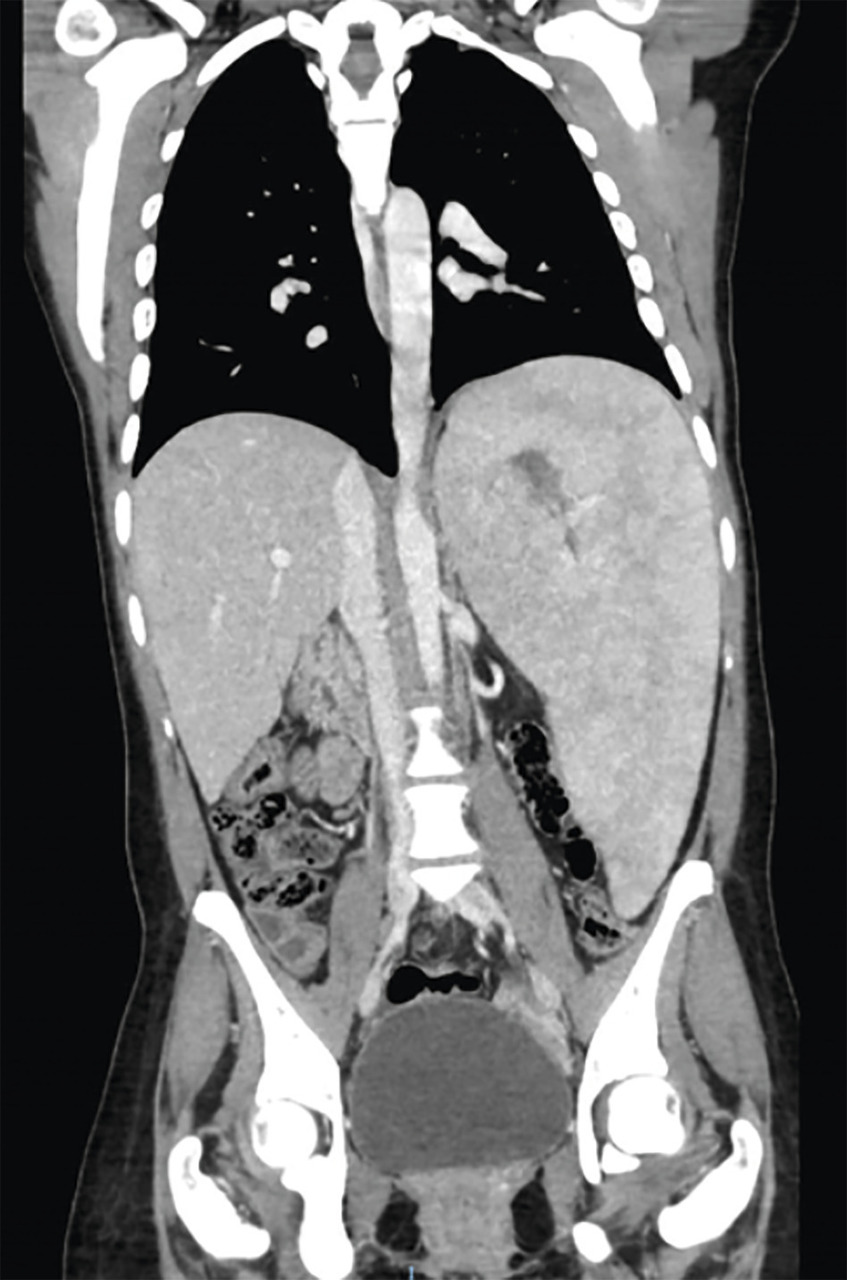

La splénomégalie est l’un des principaux signes cliniques, elle est présente chez plus de 90 % des patients, parfois massive et responsable d’une distension ou de douleurs abdominales. Il peut y avoir un hypersplénisme, participant à la thrombopénie. La splénomégalie peut se compliquer d’infarctus spléniques. Elle est souvent associée à une hépatomégalie, présente dans 60 à 80 % des cas (fig. 2 ). Des lésions focales de la rate ou du foie, appelées « gaucheromes », constituées d’amas de cellules de Gaucher peuvent être notées, pouvant poser le problème du diagnostic différentiel avec le carcinome hépatocellulaire, plus fréquent dans la maladie de Gaucher, ou avec une hémopathie.

La splénomégalie est l’un des principaux signes cliniques, elle est présente chez plus de 90 % des patients, parfois massive et responsable d’une distension ou de douleurs abdominales. Il peut y avoir un hypersplénisme, participant à la thrombopénie. La splénomégalie peut se compliquer d’infarctus spléniques. Elle est souvent associée à une hépatomégalie, présente dans 60 à 80 % des cas (

En ce qui concerne les imageries, l’échographie abdominale reste largement utilisée en première intention, car facilement disponible. Néanmoins, l’imagerie par résonance magnétique (IRM) abdominale est l’examen de choix pour évaluer les dimensions de la rate et du foie, ainsi que leur morphologie, et pour évaluer les nodules en rapport avec des « gaucheromes ». L’IRM est également l’examen de choix pour évaluer l’atteinte osseuse, pour quantifier l’infiltration osseuse par les cellules de Gaucher, l’extension des lésions, leur caractère aigu ou ancien, et pour le suivi des patients. Les radiographies osseuses sont utiles pour toute localisation symptomatique et le suivi des ostéonécroses. Les lésions rencontrées sont multiples : déformation fémorale en flacon d’Erlenmeyer (fig. 3 ), lésions lytiques, amincissement de la corticale, lésions d’ostéo-condensation, fractures. Enfin, l’ostéodensitométrie permet de détecter une ostéopénie ou une ostéoporose, fréquentes dans la maladie de Gaucher.

En ce qui concerne les imageries, l’échographie abdominale reste largement utilisée en première intention, car facilement disponible. Néanmoins, l’imagerie par résonance magnétique (IRM) abdominale est l’examen de choix pour évaluer les dimensions de la rate et du foie, ainsi que leur morphologie, et pour évaluer les nodules en rapport avec des « gaucheromes ». L’IRM est également l’examen de choix pour évaluer l’atteinte osseuse, pour quantifier l’infiltration osseuse par les cellules de Gaucher, l’extension des lésions, leur caractère aigu ou ancien, et pour le suivi des patients. Les radiographies osseuses sont utiles pour toute localisation symptomatique et le suivi des ostéonécroses. Les lésions rencontrées sont multiples : déformation fémorale en flacon d’Erlenmeyer (